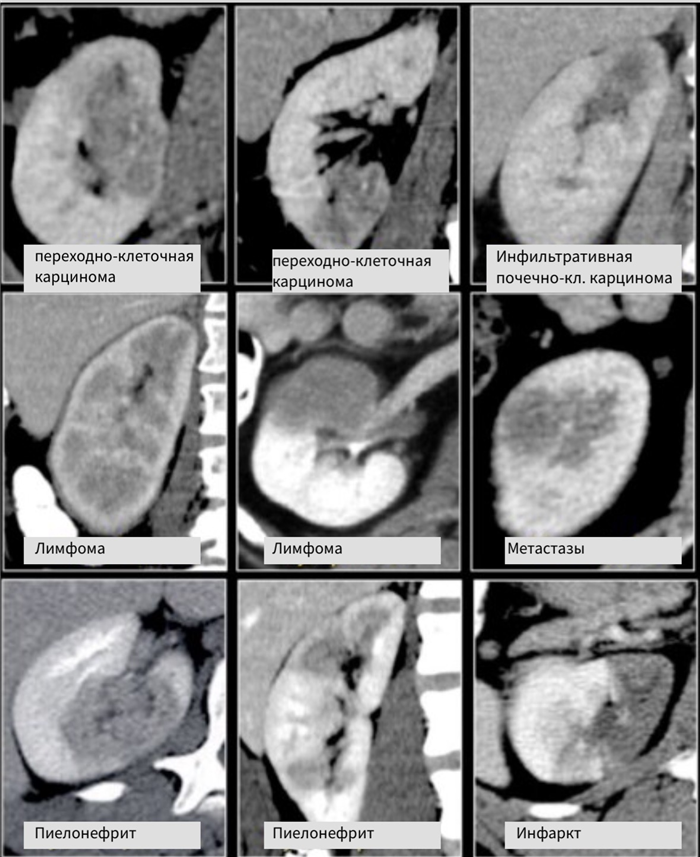

Системный подход — солидные образования почки

Бобовидные образования.

Радиологические признаки образований бобовидной формы обычно не специфичны. Данное явление заметно если обратить внимание на схожесть образований, представленных на рисунке. Дифференциальный диагноз обычно строят, исходя из клинических данных и, соответственно, данных визуализации.

Инфильтрирующее почку по центру образование у пожилого пациента соответствует переходно-клеточному раку почки. Инфильтрирующее почку по центру образование у молодого пациента с серповидной перегородкой внутри больше соответствует медуллярной карциноме почки. Мультифокальные и билатеральные или диффузные образования почки в сочетании с лимфоаденопатией, а также с вовлечением в патологический процесс других органов характерны для лимфомы.

Мультифокальные и двусторонние поражения почек характерны для злокачественных образований, в частности для метастазирования. У пациентов с клиникой характерной при инфекции, конечно же, в первую очередь нужно подозревать пиелонефрит. Для инфаркта почки характерно клиновидное поражение почки.